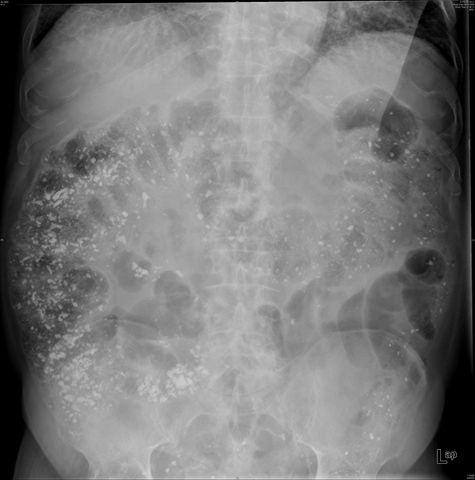

Diverticulosis de colon.

Diverticulosis de colon. Megacolon.